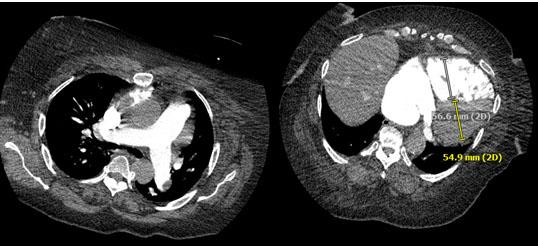

We considered septic shock but she had no fever or leukocytosis. Although patient had bradycardia instead of tachycardia, obstructive shock secondary to pulmonary embolism is considered given her risk factors (obesity and recent immobilization), new right axis deviation and elevated RVSP. We considered fat embolism syndrome; however, she did not have the classic triad of hypoxemia, petechia, and altered mental status. Her computed tomography of the chest did not reveal findings suggestive of acute respiratory disease syndrome. Further, the incidence of fat embolism is low at 0.17%, and typically due to femur fracture [7]. Bedside TTE showed normal LVEF but had signs of right ventricular strain, further underscoring this suspicion. She underwent computed tomography pulmonary angiogram pulmonary embolism and enlarged right heart chambers with reflux of contrast within the hepatic veins (Figure 4).

Figure 4: Computed tomography pulmonary angiogram showed bilateral pulmonary embolism and enlarged right heart chambers with reflux of contrast within the hepatic veins.